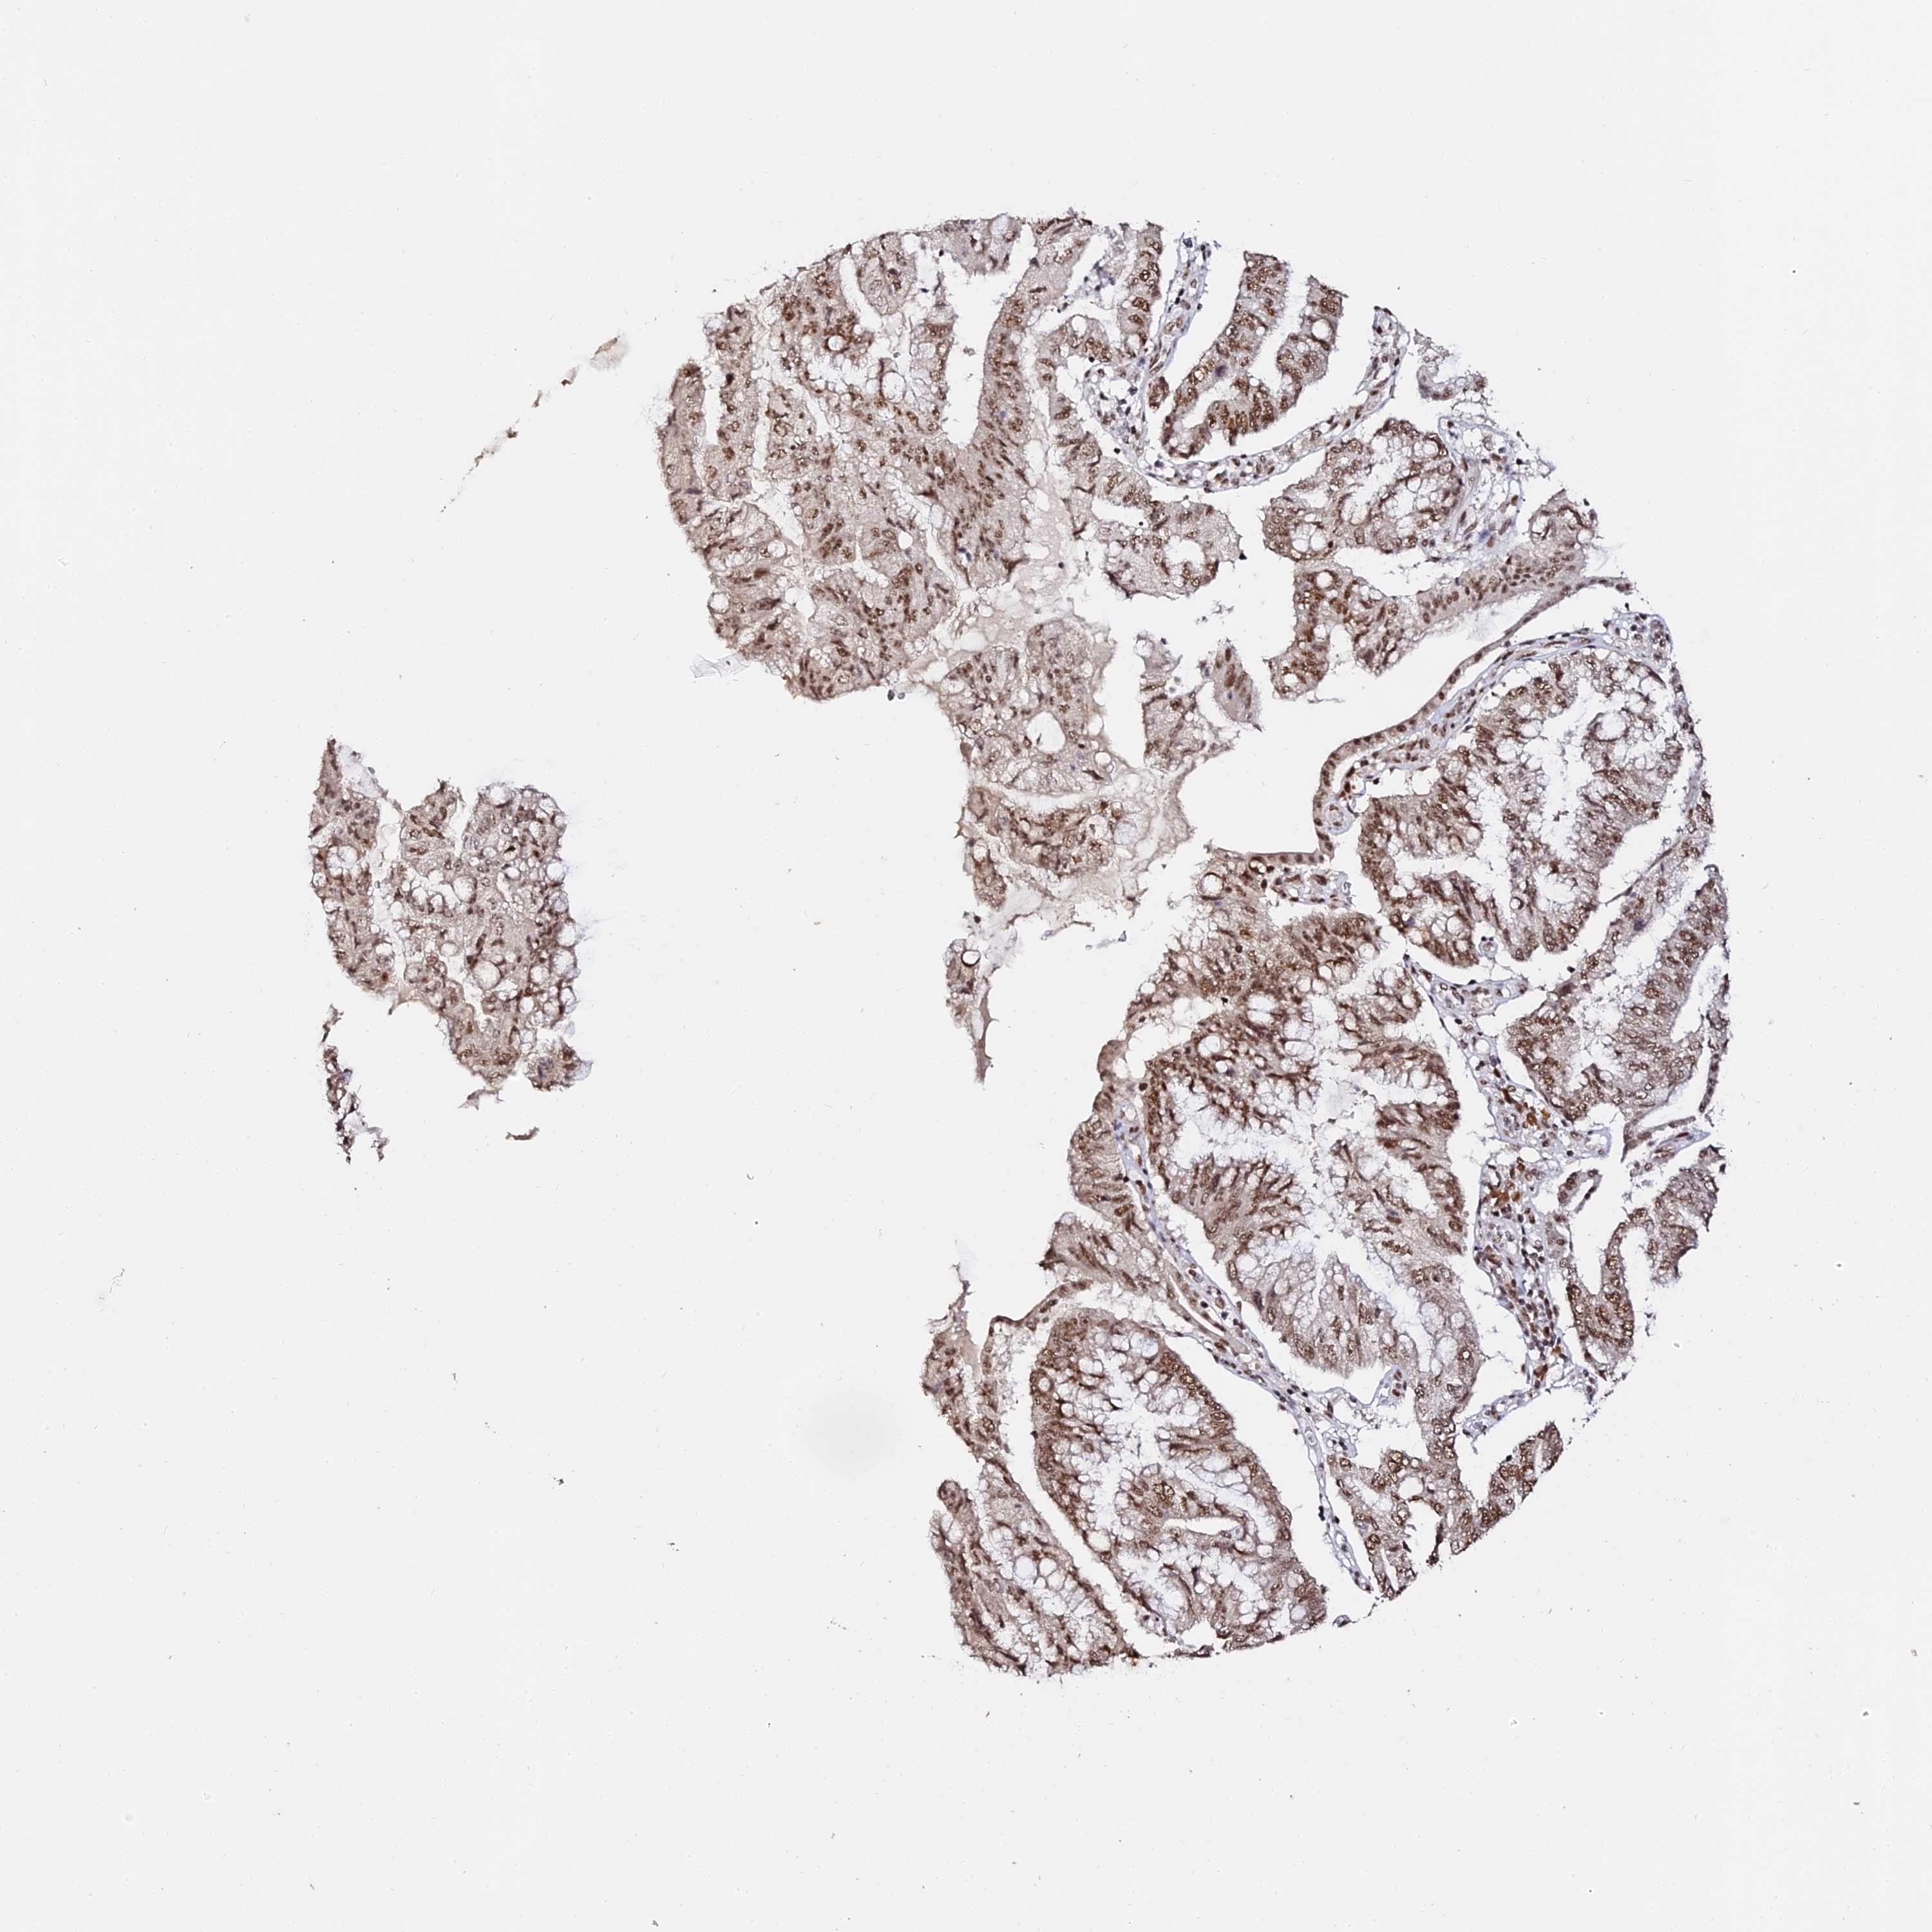

PANCREATIC CANCER - Protein expressioni

A mouse-over function shows sample information and annotation data. Click on an image to view it in a full screen mode. Samples can be filtered based on level of antibody staining by selecting one or several of the following categories: high, medium, low and not detected. The assay and annotation is described here.

Note that samples used for immunohistochemistry by the Human Protein Atlas do not correspond to samples in the TCGA dataset.

Antibody stainingi

Antibody staining in the annotated cell types in the current human tissue is reported as not detected, low, medium, or high, based on conventional immunohistochemistry profiling in selected tissues. This score is based on the combination of the staining intensity and fraction of stained cells.

Each image is clickable and will lead to virtual microscopy that enables deeper exploration of all samples and also displays staining intensity scores, fraction scores and subcellular localization as well as patient and tissue information for each sample.

Antibody HPA039057

Staining

High

Medium

Low

Not detected

Intensity

Strong

Moderate

Weak

Negative

Quantity

>75%

75%-25%

<25%

None

Location

Nuclear

Cytoplasmic/membranous

Cytoplasmic/membranous,nuclear

Adenocarcinoma, NOS